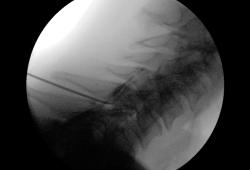

Onder röntgendoorlichting wordt de naald nauwkeurig gepositioneerd. De huid wordt eerst lokaal verdoofd, wat een kort branderig gevoel kan geven. Door deze verdoving voelt het inbrengen van de naald meestal enkel als druk. Eenmaal de juiste positie bereikt is, wordt het medicijnmengsel geïnjecteerd. Hierbij kan een warmtegevoel optreden in één of beide armen – dat is normaal.